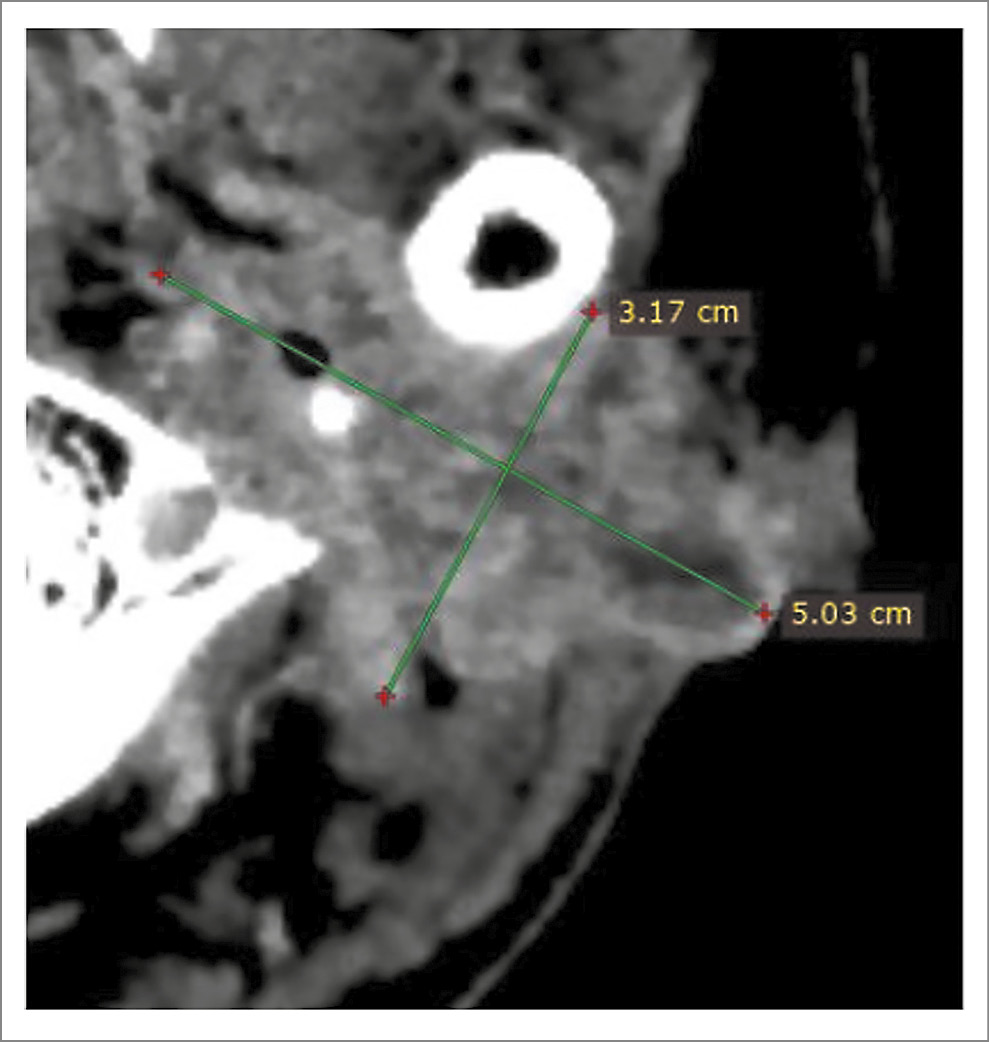

По данным КТ головного мозга, головы и шеи, органов грудной клетки, органов брюшной полости с внутривенным контрастированием от 20.07.2023 (рис. 1): слева отмечается снижение пневматизации среднего уха, сосцевидного отростка за счет патологического содержимого, деструкция костных структур пирамиды левой височной кости, слуховые косточки визуализируются фрагментарно. В мягких тканях вокруг сосцевидного отростка левой височной кости, левой околоушной области – патологическая опухолевая инфильтрация размерами 50×32 мм. Лимфоузлы шеи не увеличены. В остальном без особенностей.

Рис. 1. Результаты КТ головы от 20.07.2023: патологическая опухолевая инфильтрация мягких тканей вокруг сосцевидного отростка левой височной кости, левой околоушной области.